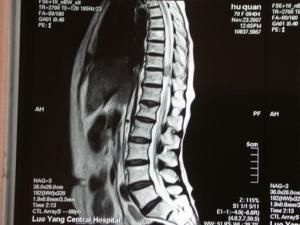

3.CT 與MRI檢查

CT掃描難以做出確切診斷。腫瘤在MRIT加權圖像上呈髓外低信號瘤灶,在T加權圖像上呈高信號瘤灶;增強掃描:實體性腫瘤呈均勻強化,囊性腫瘤呈環形強化,少數腫瘤呈不均勻強化。另視腫瘤所在解剖層次不同,出現相應的脊髓移位。